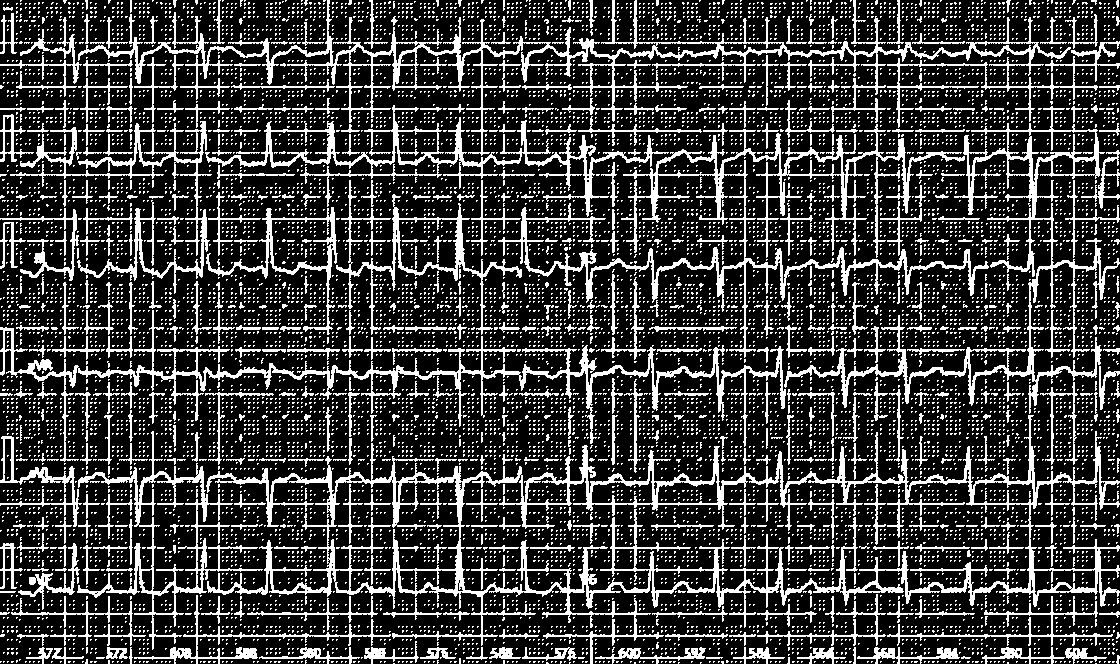

处理效果演示

从纸质心电图记录中提取数字ECG信号的Python工具

支持网格检测、信号保护、几何校正与物理单位标定